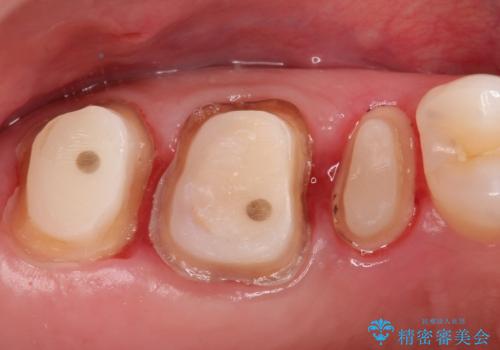

- 以前、他院で保険治療の被せ物を入れた歯が欠けてしまったことを主訴に来院されました。

その他の歯も適合が悪く治療が必要でしたので、3歯まとめて治療を行いました。

歯肉縁下マージンに対して矯正的挺出などの治療の選択肢や、根管治療の提案をしましたが、患者様との話し合いにより歯冠修復のみ行なっております。